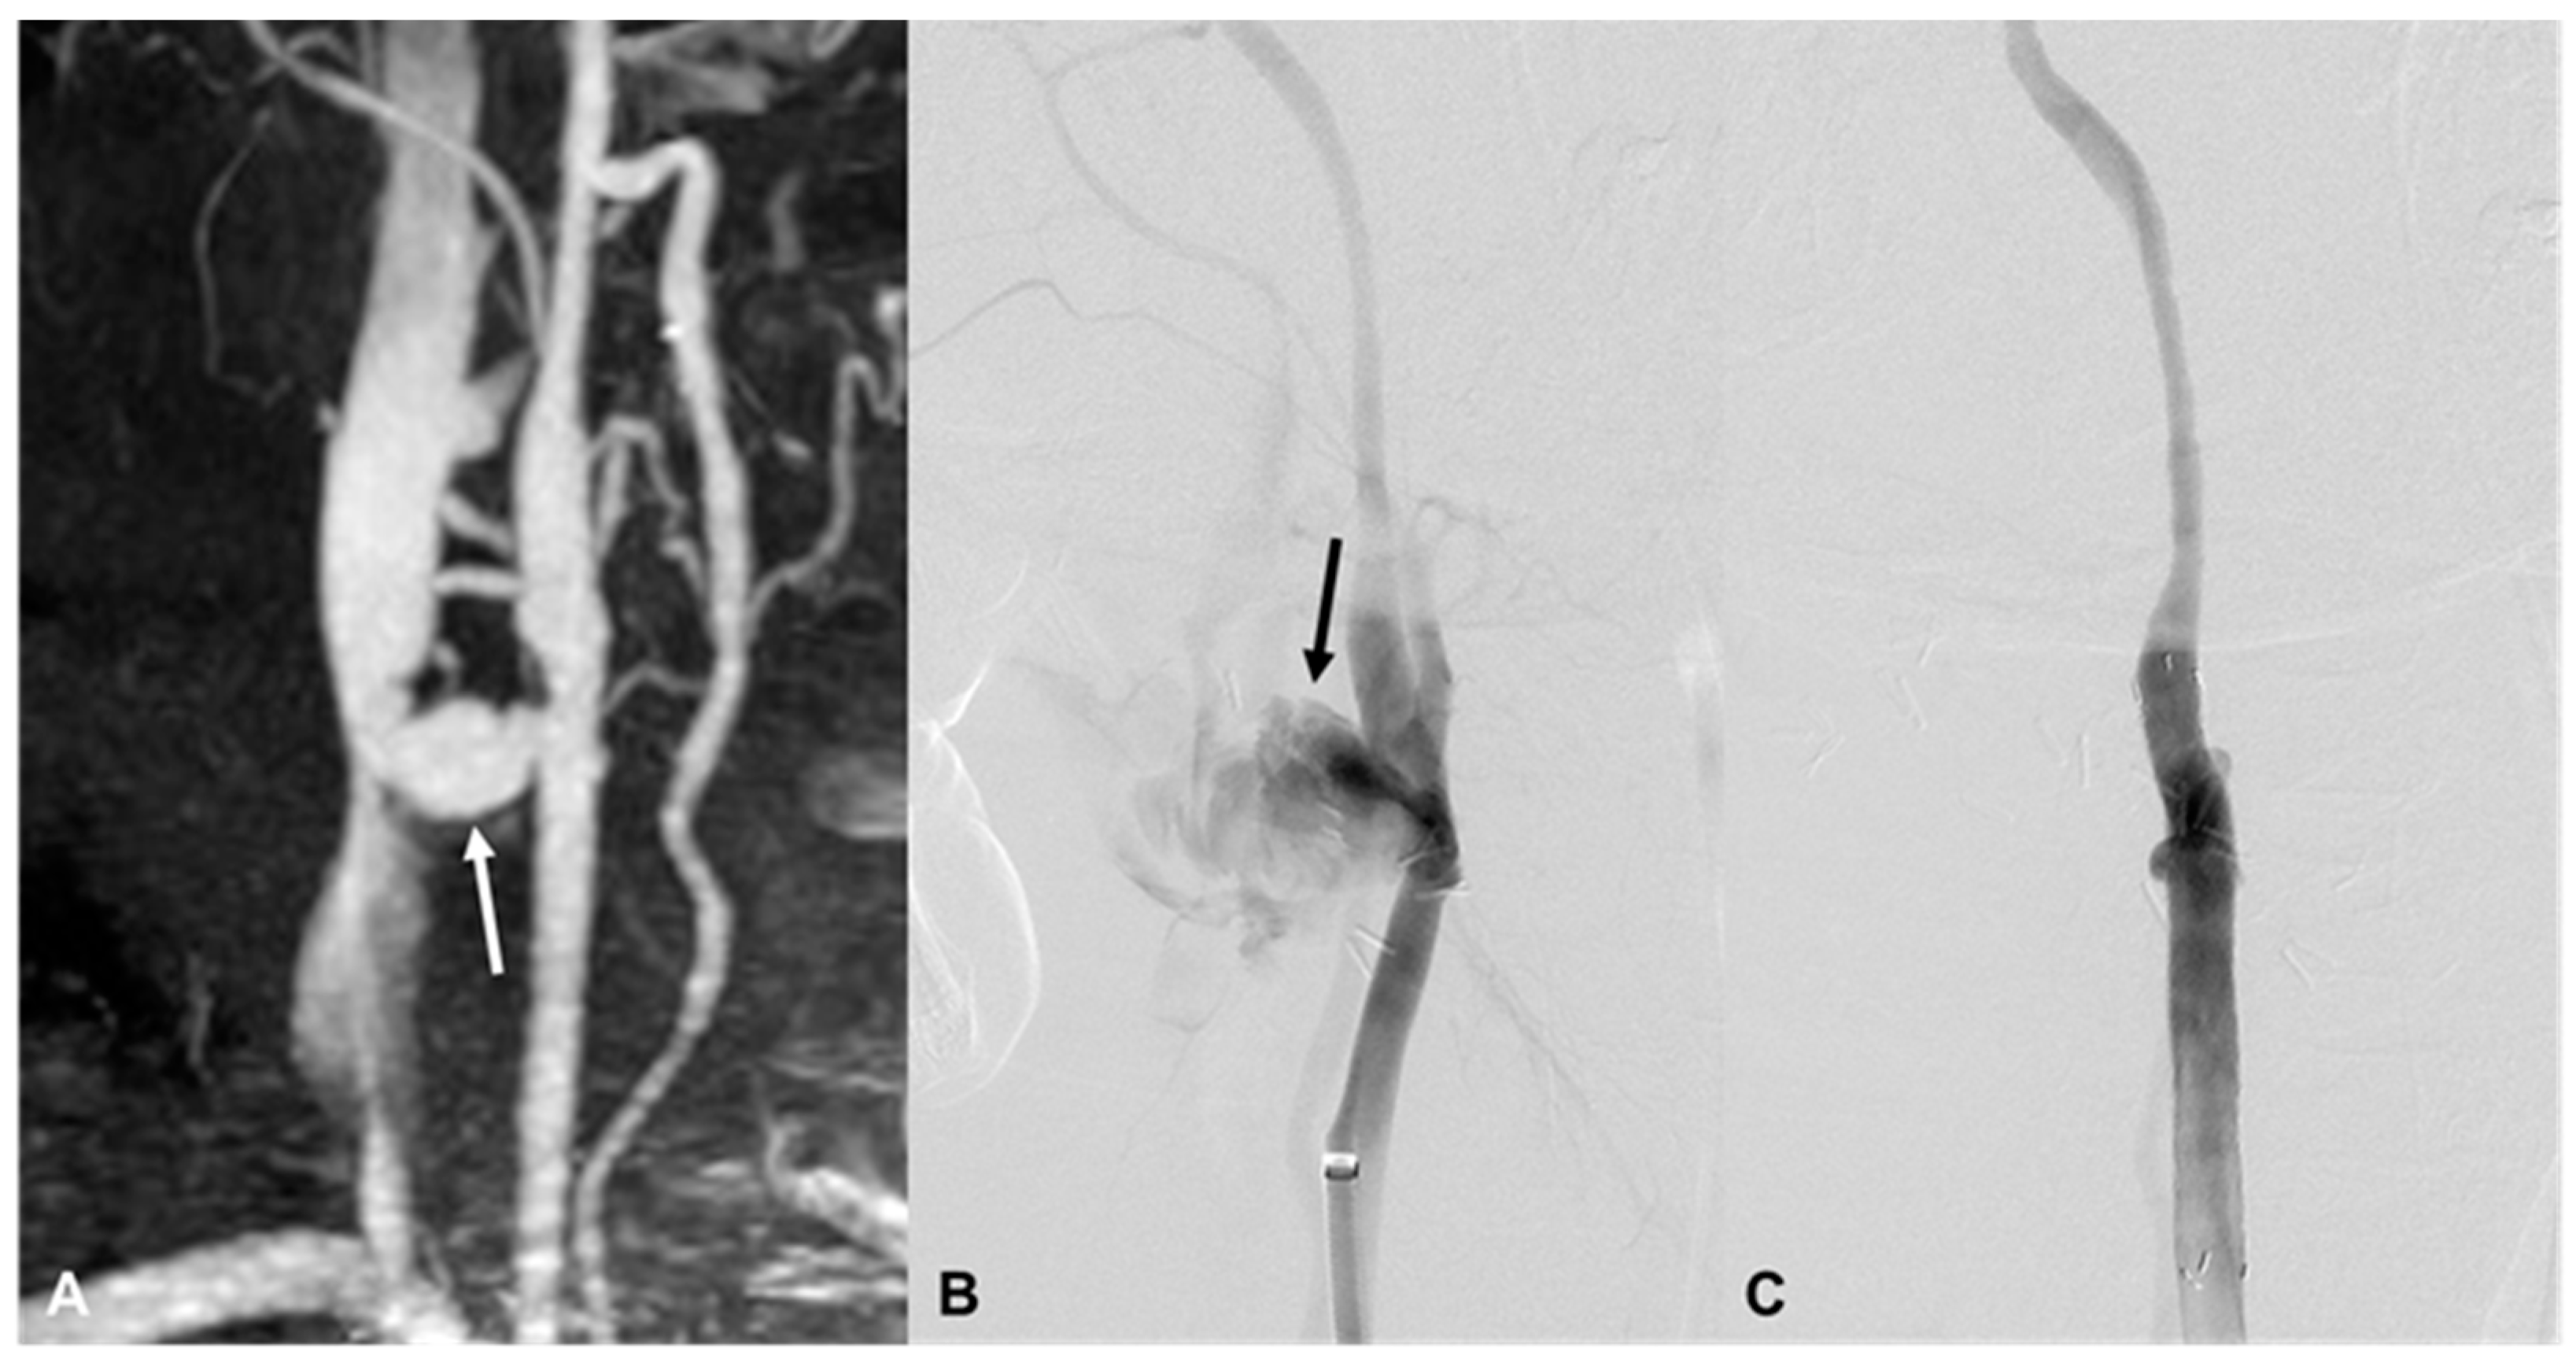

| 10 | 25/M | Blunt | Ear bleeding | Hematoma, retropharyngeal space | EV, L VA (V2) | bStent, coil | Brain death 12 d |

| 13 | 53/F | Stab | Bleeding | Hematoma, L neck | EV, L VA (V2) | Coil, bStent | Stable 1416 d F/U |